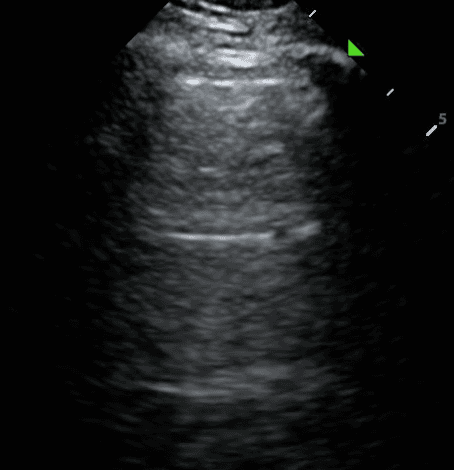

To identify whether the lungs are normal, look for the following features:

Lung Sliding:

A Lines:

The absence of lung sliding and A lines indicates lung pathology. The next step is to search for features of lung consolidation.